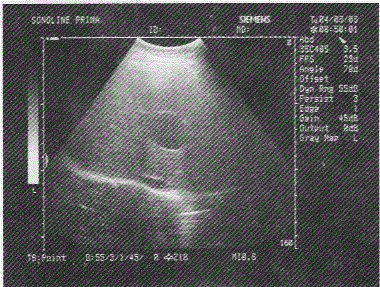

成年患者肝脏超声表现如图,诊断为

声像图显示肝右叶内可见一无回声暗区,边清壁薄。